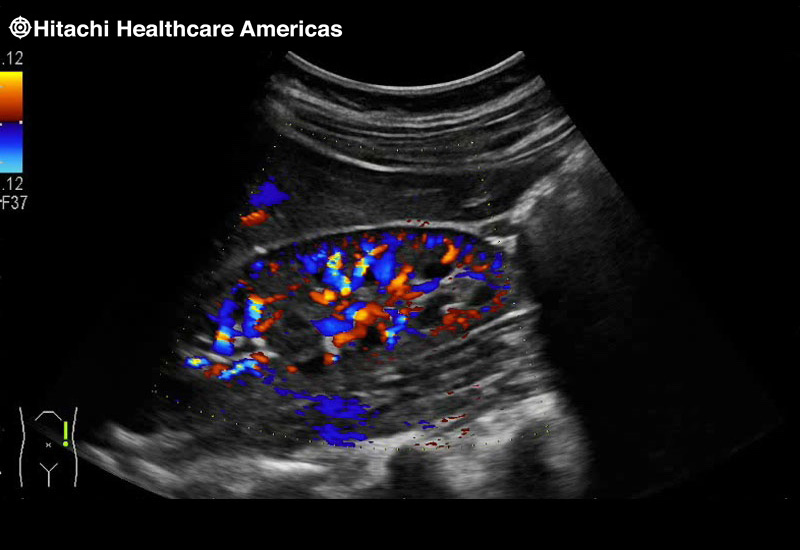

Superior guidance for all applications

Fujifilm Healthcare Americas is committed to designing tools that help surgeons navigate inside the human body and provide the necessary information to immediately make critical surgical decisions.

Fujifilm Healthcare's dedication to Surgeons provides outstanding ultrasound technology, professional support and the specialized tools necessary to best perform comprehensive real-time ultrasound imaging in Breast Surgery, General Surgery, Laparoscopic Surgery, Neurosurgery, Robotic Surgery and Surgical Oncology.

Fujifilm Healthcare’s ARIETTA Precision features state-of-the-art digital architecture and advanced imaging technologies to redefine the capabilities of surgical ultrasound.

Imaging Clearly Defined

State-of-the-art digital architecture and advanced imaging features to redefine the capabilities of surgical ultrasound.